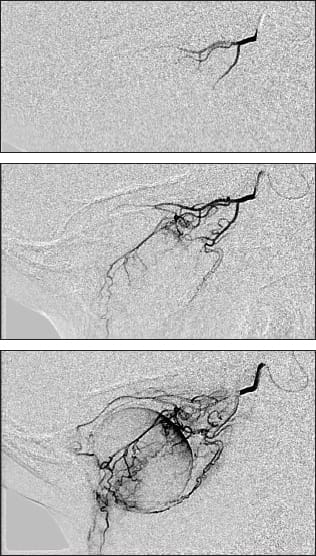

Figure 1. Left eye of a child with large macular retinoblastoma before treatment (top) and after intra-arterial melphalan and focal laser consolidation (bottom).